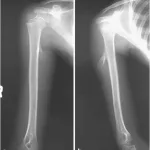

小指の基節骨の内軟骨腫の普通写真(A), X線写真(B, C), CT(D, E), MRI(F).

引用元:Oliveira RK. Intramedullary fixation with cannulated screw after resection of enchondroma in the hand: Technique description and case series. J Hand Surg Glob Online. 2023. 5.

12時から, 高校生の小指基節骨の内軟骨腫切除術を執刀.